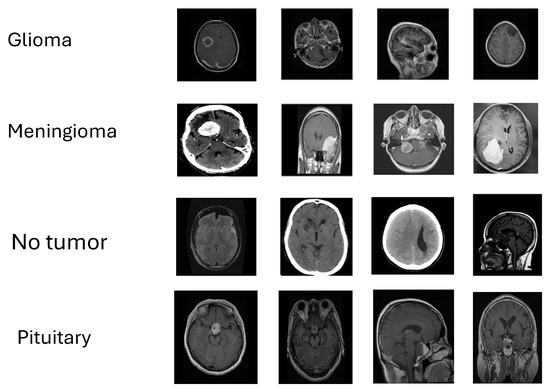

Data preparation processes, including resizing, are advantageous in enhancing the classification models, as emphasized by Gu et al. [15] and Alsubai et al. [14]. The breadth and versatility of this data collection enables thorough testing and provides deeper insights into the performance of various classification algorithms [22,26]. The diversity of the validation dataset is obvious from the example photographs of the four brain tumor kinds given in Figure 1.

Figure 1. Representative MRI slices from the four study classes—glioma, meningioma, pituitary tumor, and no tumor—illustrating appearance variability used for validation.